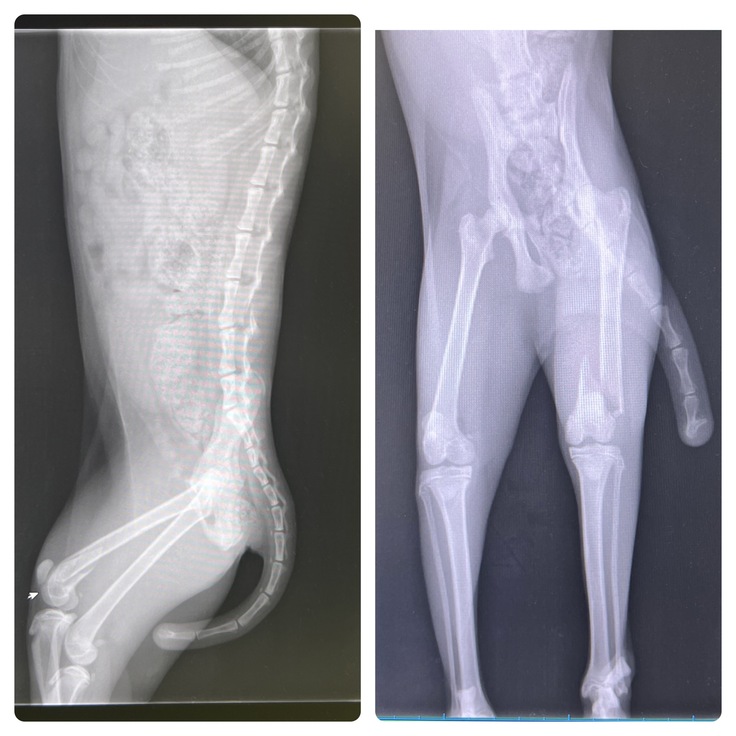

▲術前検査の左大腿骨のレントゲン写真

⑤10月7日 手術当日

開けてみないとわからないが骨の状態が良ければ中に支柱を入れるだけの手術の予定でした。

その場合は通院も少なく済み、再手術もいらないので一番いいと話しておりましたが、

開けてみると骨はレントゲンには映らないような細かなヒビが入っていたため、外からも固定が必要になり、

消毒など術後に定期的な通院と骨が完治してからまた摘出のために麻酔をかけた状態の手術が必要な外側固定もついたと言われました。

▲術後の左大腿骨のレントゲン写真

踵については、とても薄い骨の骨折なので固定は難しく、可動域もある部位のため、外からのしっかりとしたテーピングによる固定で完治を目指すことになりました。